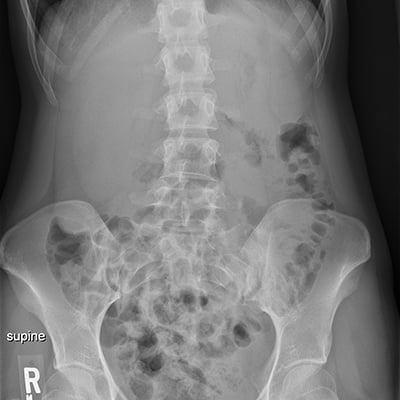

This module will help you achieve optimal images of the chest and abdomen, including AP and lateral decubitus chest examinations, and supine, upright, and decubitus abdomen examinations are also covered. Patient positioning, technical settings, and patient instructions are discussed. Descriptions and images of the expected anatomical structures are included, as well as image evaluation criteria.